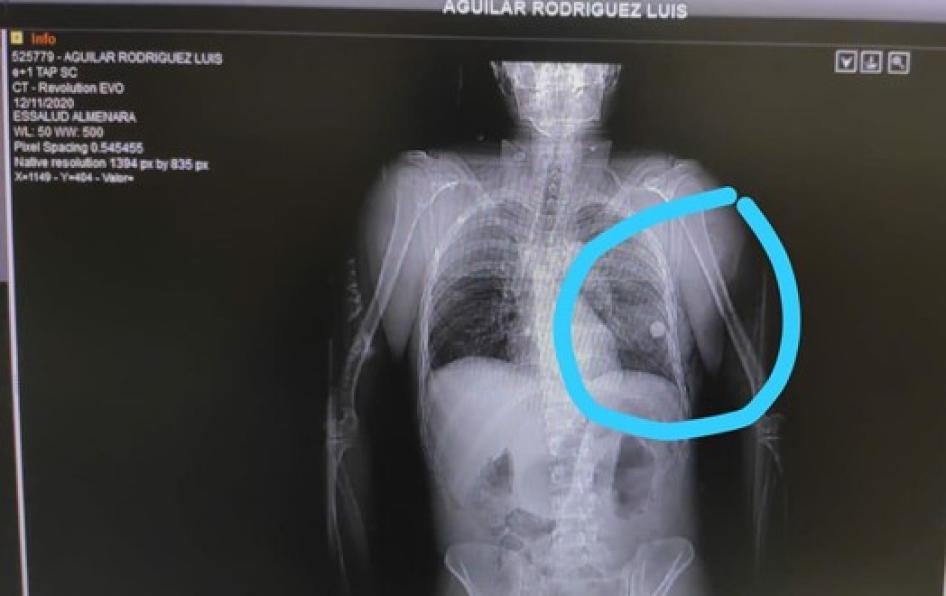

• Dos manifestantes encontraron a Luis Aguilar Rodríguez, de 26 años, con una herida sangrante en el pecho en la Avenida Abancay el 12 de noviembre y lo llevaron a un hospital, según relató su madre. Después de la cirugía, los médicos le dijeron que el objeto que se había alojado en su pecho y le había provocado daño en los pulmones era una canica de vidrio, que extrajeron durante el procedimiento. Aguilar Rodríguez estuvo hospitalizado hasta el 30 de noviembre.

Radiografía que muestra una canica alojada en el pulmón de Luis Aguilar Rodríguez. Fotografía proporcionada por la familia de Luis Aguilar Rodríguez.